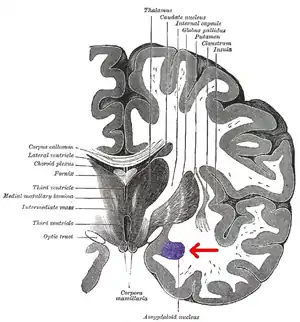

![]() Subdivisions of the amygdala | |

The regions described as amygdala nuclei encompass several structures of the cerebrum with distinct connectional and functional characteristics in humans and other animals.[5] Among these nuclei are the basolateral complex, the cortical nucleus, the medial nucleus, the central nucleus, and the intercalated cell clusters. The basolateral complex can be further subdivided into the lateral, the basal, and the accessory basal nuclei.[3][6][7]